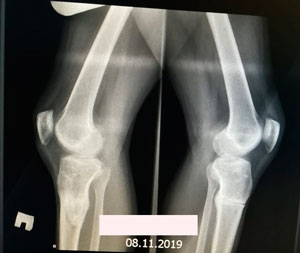

Дата операции - 18.06.2019г.

Дата снятия аппаратов - 20.09.2019.

Срок сращения - 93 дня.